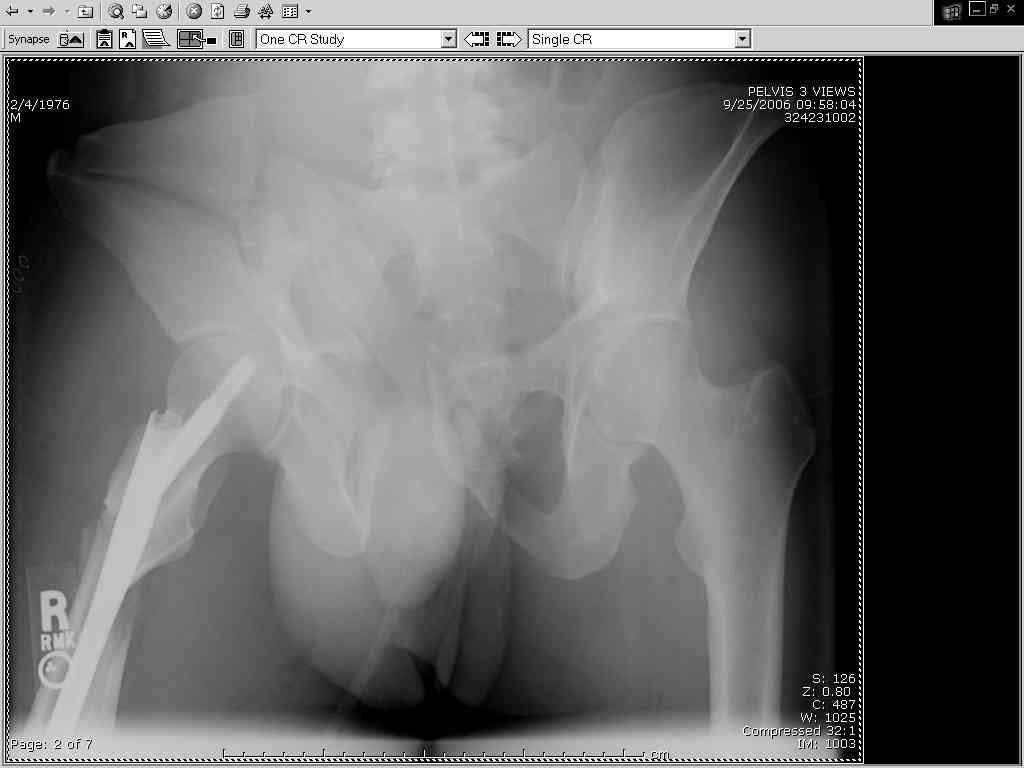

Thanks Adam - I agree it's not a pure APC (is there really such thing as a pure force vector strictly in the x,y or z plane?). I stand corrected. Maybe a hybrid APC (ext rot of L hemipelvis, symphysis disruption, ext rot of R anterior innominate) plus vertical shear as well with 3 or-so cm of cephalad migration of the R ilium. Maybe just "C-type".....

It almost looks to me like an extra-articular both column fx, in addition to the pelvic component. It has the typical triangular fragment and the OO view has a hint of the spur. You may be able to get it all with plates. I would consider fixing the crest first, then a long plate for both symph and iliac portion. SI may close with reduction of symphisis. Looks like the inferior portions are intact. I like your plan as well. You will probably solicit lots of opinion. Good luck. Look forward to post op view.